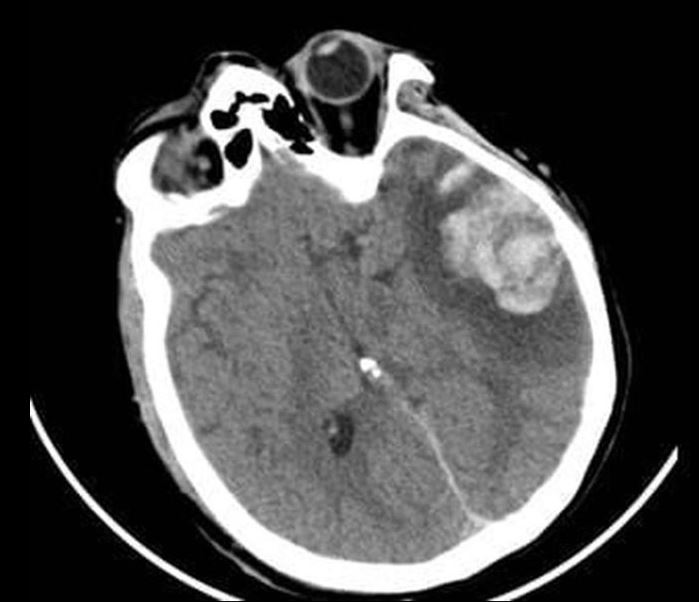

Phim CT não của 2 bệnh nhân

Tại Bệnh viện Nhân dân 115, bệnh nhân G.A nhập viện trong tình trạng hôn mê sâu, phải thở máy nội khí quản. Kết quả chụp CT sọ não cho thấy dập não xuất huyết rải rác nhiều vị trí, phù não lan tỏa nặng, tiên lượng rất dè dặt, nguy cơ tử vong cao. Bệnh nhân được điều trị tích cực tại Đơn vị Hồi sức ngoại khoa, Khoa Gây mê Hồi sức với sự theo dõi sát sao của ê-kíp chuyên môn.

Người mẹ, bà G.N. cũng trong tình trạng rối loạn tri giác, dập não thái dương lượng lớn. Sau hội chẩn kỹ lưỡng, các bác sĩ quyết định lựa chọn phương pháp điều trị bảo tồn nhằm hạn chế tối đa tổn thương thứ phát. Hướng điều trị này cho thấy hiệu quả rõ rệt khi người bệnh dần tỉnh táo, cải thiện khả năng giao tiếp và chức năng ngôn ngữ. Sau 10 ngày điều trị tại Khoa Ngoại thần kinh, bà G.N. hồi phục tốt và được xuất viện.